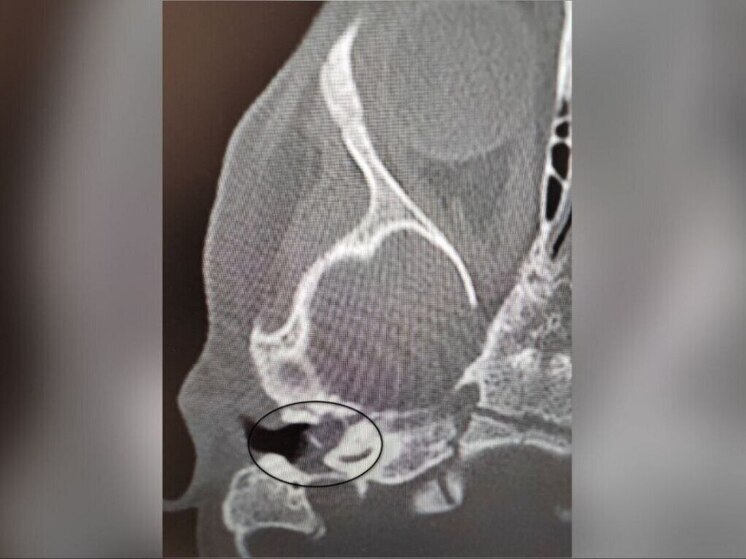

Специалисты Воронежской областной детской клинической больницы успешно провели уникальную операцию. Двухлетней девочке с редким заболеванием "врожденная холестеатома" не только спасли жизнь, но и восстановили слух. Об этом сообщили в пресс-службе регионального Министерства здравоохранения.

Проблемы начались после обычного ОРВИ, когда у ребенка появились боли в ухе. Ситуация усугубилась развитием пареза лицевого нерва, из-за чего ослабли мимические мышцы. Проведенное обследование подтвердило диагноз: врожденное кистозное образование в среднем ухе. Для сохранения здоровья и слуха девочки требовалось экстренное хирургическое вмешательство.

Операцию провел Антон Мащенко, заведующий отделением больницы. Во время сложной процедуры врачи удалили кистозное образование, восстановили функцию лицевого нерва и систему звукопроведения, что позволило не только устранить угрозу, но и сохранить слух ребенка.